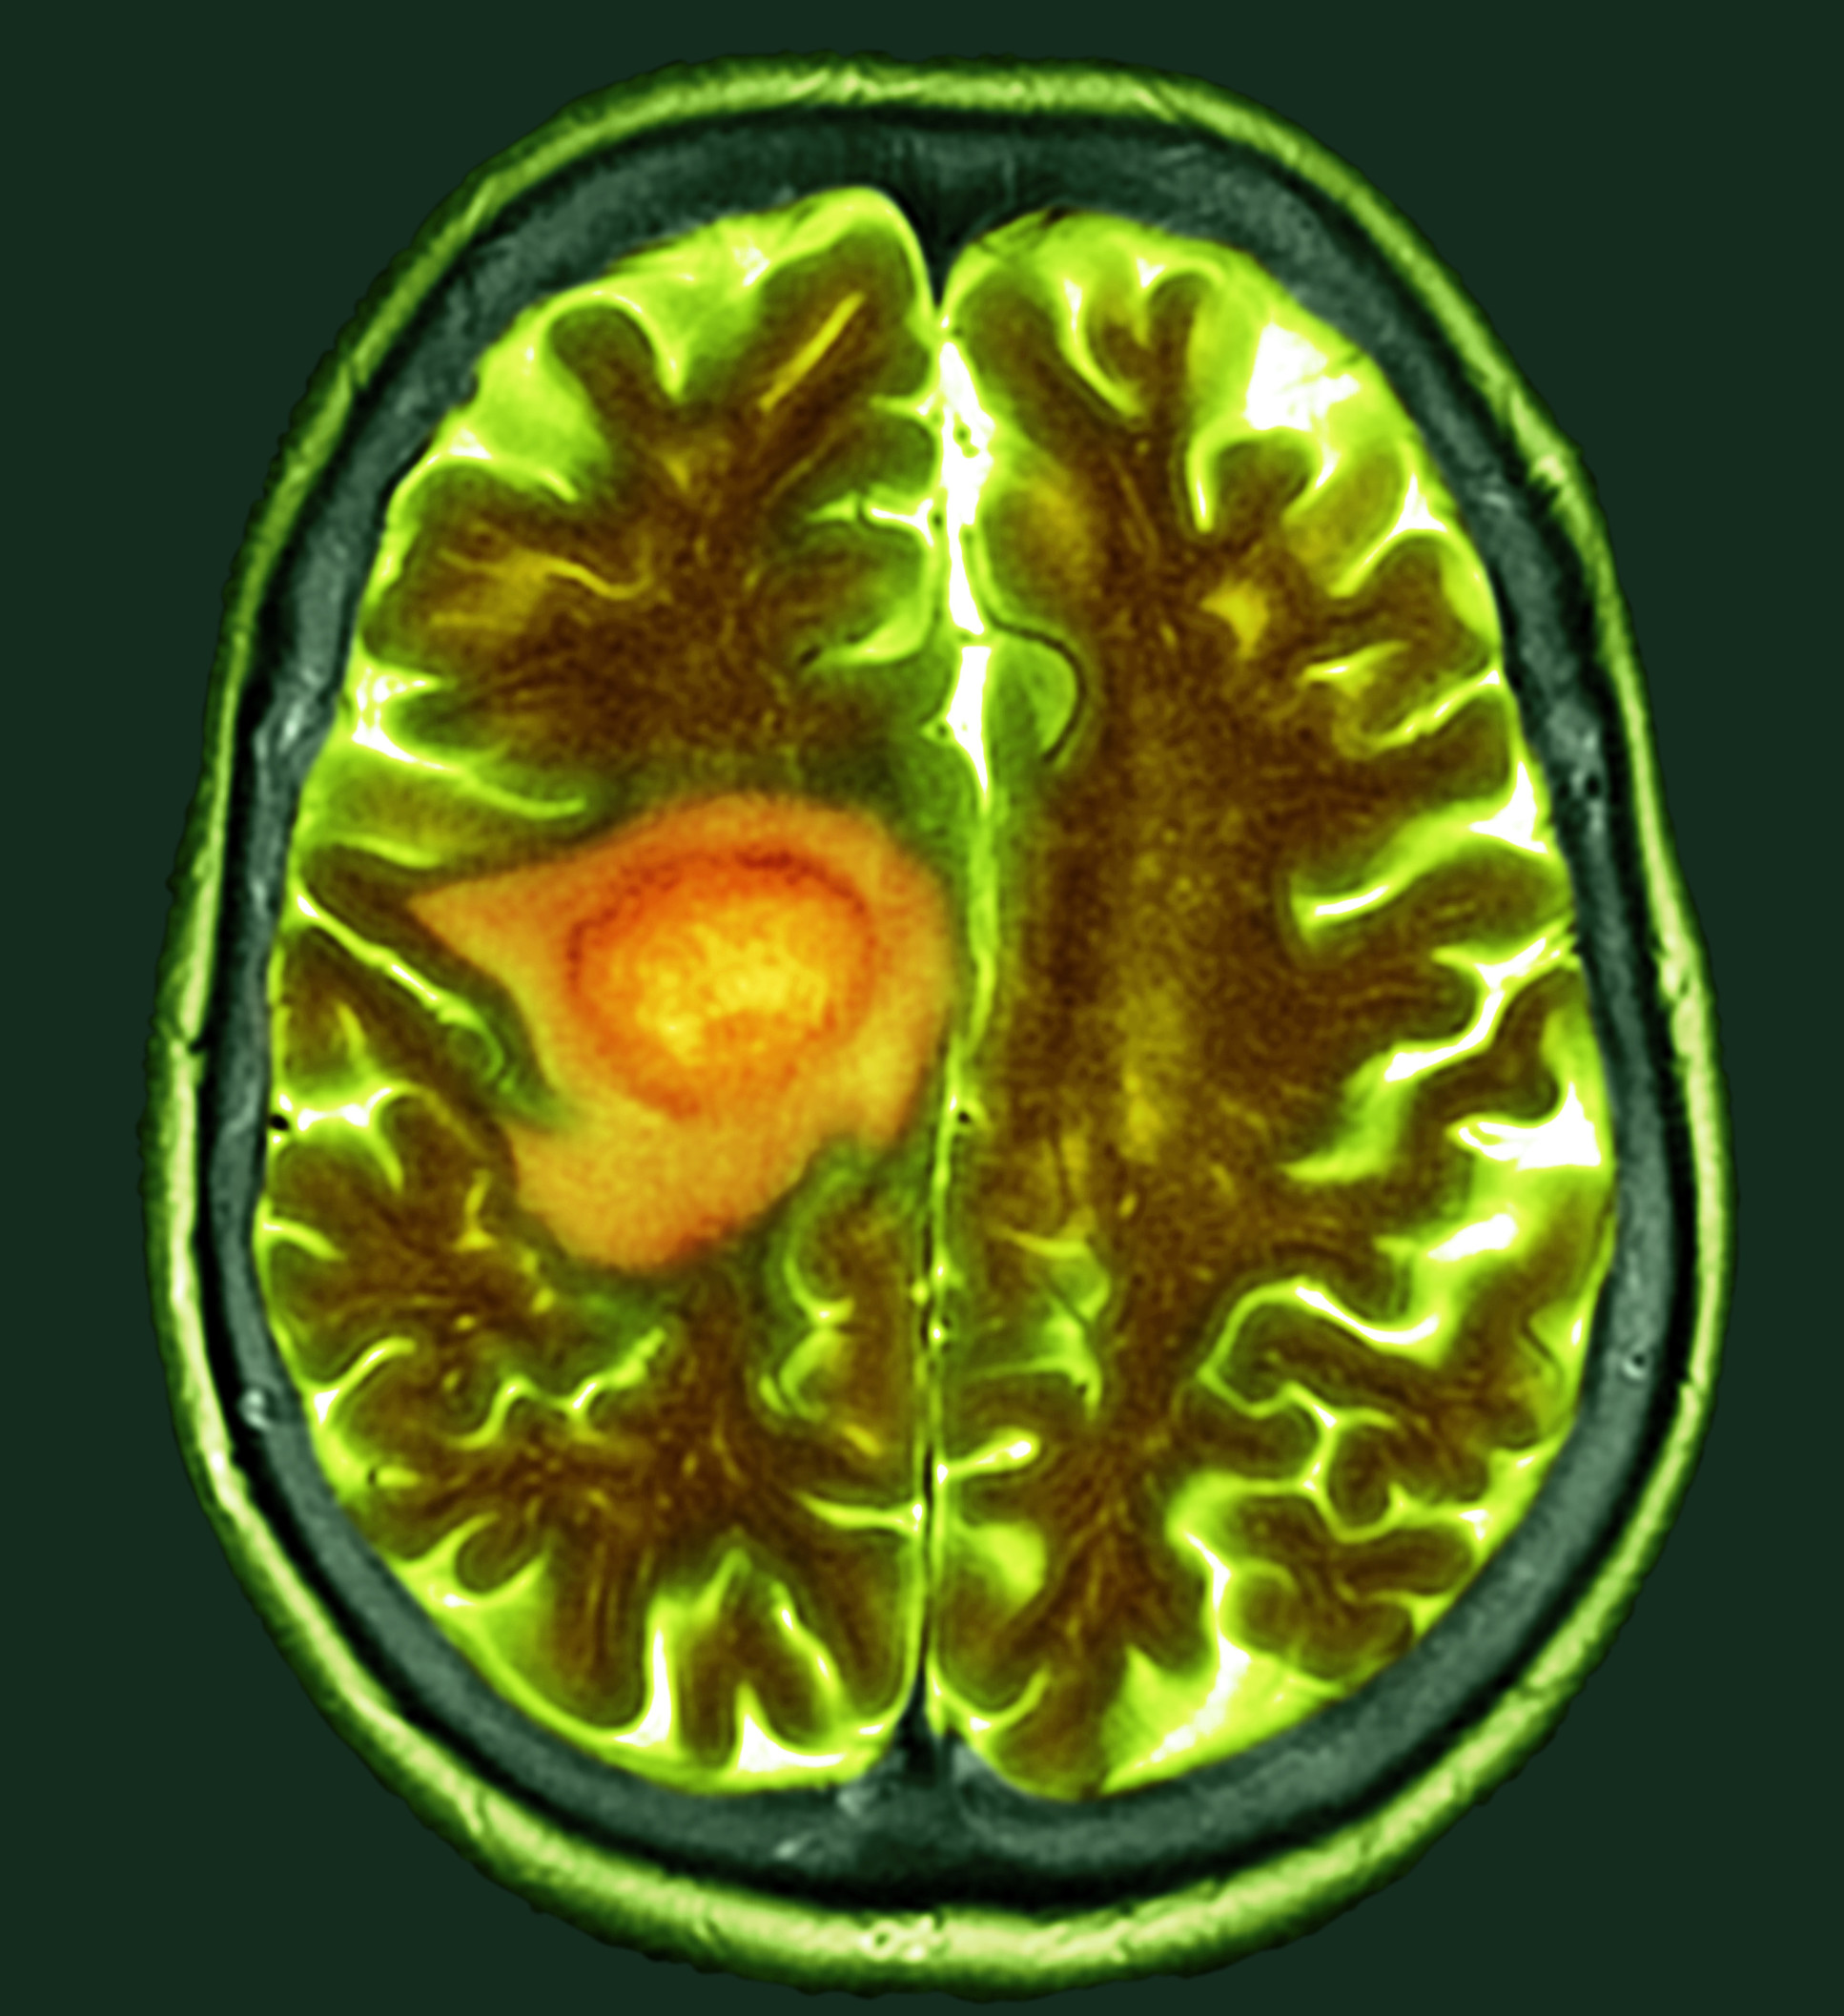

CT scan of glioblastoma brain cancer

Glioblastoma is one of the most aggressive forms of brain cancer.